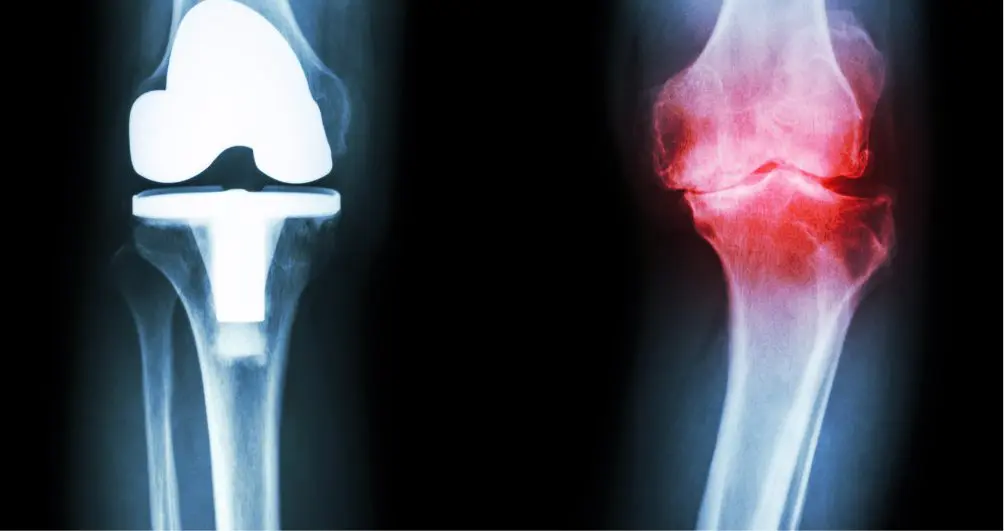

Rappelons que l’arthrose est une pathologie qui génère des douleurs et des raideurs articulaires à la suite d’une dégénérescence du cartilage des articulations. La supplémentation en glucosamine et chondroïtine vise donc à prévenir cette dégénérescence et à stimuler la production cartilagineuse ainsi qu’à réduire les symptômes.

Des études menées en 2015, montrent qu’après 6 mois de consommation, cette association réduit la douleur, la raideur, la limitation fonctionnelle et les complications. Et qu’après 2 ans, il a été démontré qu’il y avait une diminution significative du rétrécissement de l’interligne articulaire.

Certaines études montrent en effet que la chondroïtine soulage la douleur causée par l’arthrose du genou et de la hanche.

D’autres études montrent que la glucosamine est efficace dans la réduction des douleurs arthrosiques.

Combiner la consommation de la chondroïtine avec la glucosamine améliore l’effet analgésique et anti-inflammatoire des deux substances. L’association des deux éléments est pertinente puisque les mécanismes d’action de ces deux molécules sont différents et complémentaires.

On estime que l’état des arthrosiques est amélioré dans environ 80% des cas.